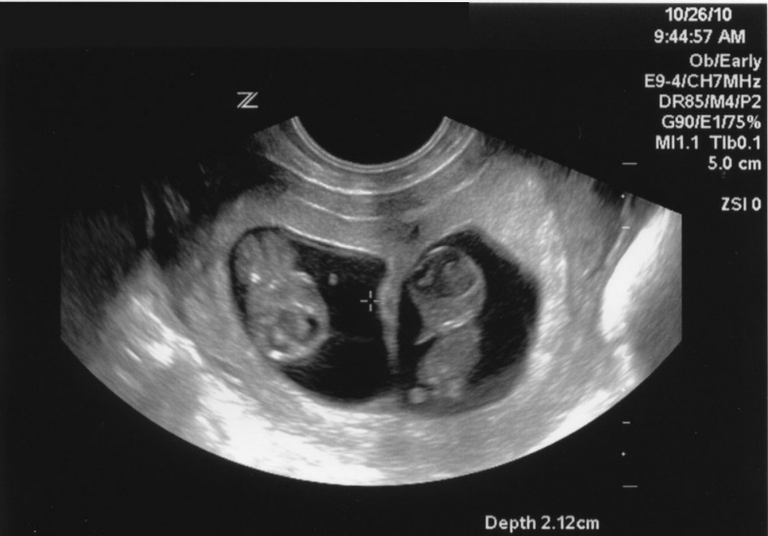

5- احتمالية إنجاب التوائم

عندما يتم إرجاع الأجنة إلى رحم الأم يُجرى إرجاع من 1 إلى 3 أجنة حسب حالة الأم، ما يزيد من احتمالية اكتمال الحمل في الأجنة كلها.